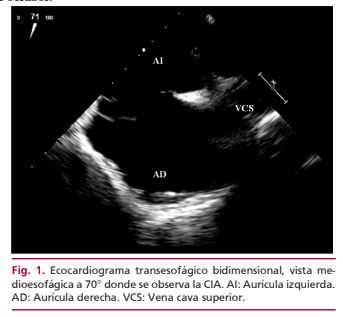

CIA multifenestrada, valor del Ecocardiograma Transesofágico 3D para el diagnóstico y como guía en la terapia de cierre percutáneo

IMÁGENES EN CARDIOLOGÍA